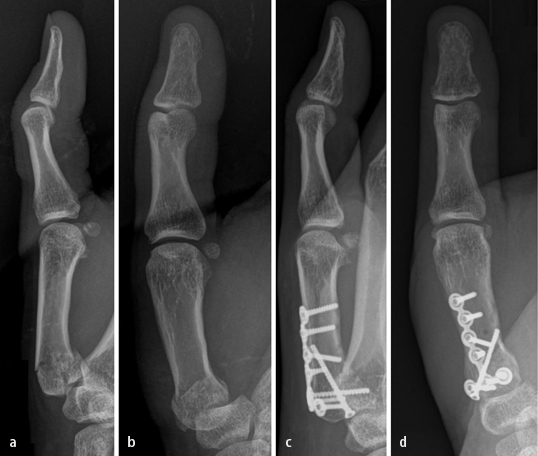

Ligamentäre Verletzungen und Bandinstabilitäten der ...

Ligamentäre Verletzungen und Bandinstabilitäten der ... from media.springernature.com